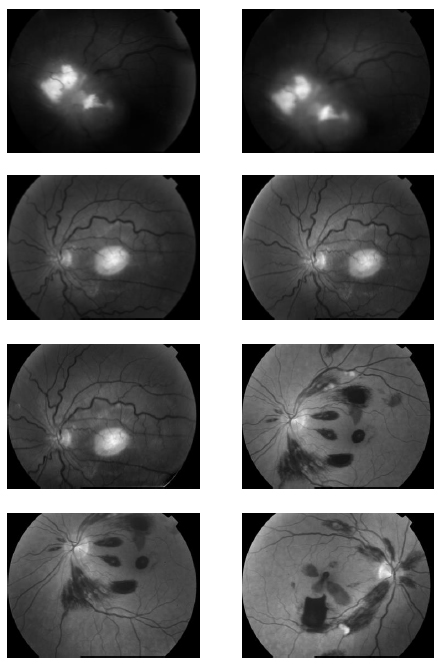

In the first part of the experiments, the effects of the score and penalty values for two iteration values were studied. All runs have been done for two neighborhood sizes of 3×3 and 5×5. Samples of the original retinal images with hard exudates are shown in (Figs. 1-3) show noisy images and the images denoised by the ripplet transform-based denoising method presented in this paper. Segmented images of retinal images are shown in Fig. (4). The images in Fig. (4) correspond to the implementation of the proposed method with a marginally optimum set of parameters, while their numerical results are given in Table 2. The results of statistical analysis on the score and penalty assignments are given in Table 2 while the proposed method is used with and without the denoising process. It is shown that the optimum score and penalty values stand about 0.01 and 0.02 while the product of score/penalty values and the number of iterations is important. The denoising process improves the statistical parameters of about 4-6%. It is also shown that for our dataset images, the neighborhood size of 5×5 which is an extended Moore neighborhood, leads to better results as compared to the simple Moore neighborhood.

![]() |

Fig. (3). Denoised Retinal Images by cycle spinning and ripplet transform. |